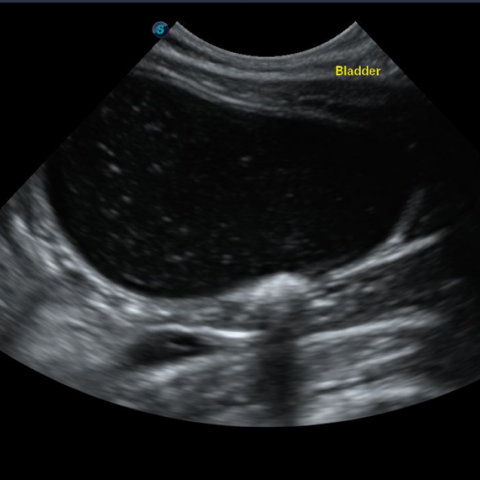

±âº»ÀûÀ¸·Î ¿µ»ó °Ë»ç(¹æ»ç¼± °Ë»ç, ÃÊÀ½ÆÄ °Ë»ç)¿Í ¿ä°Ë»ç·Î ¹æ±¤ÀÇ Æó»ö ¿©ºÎ, ¿°Áõ, °á¼®, ¼¼±Õ °¨¿° ¿©ºÎ¸¦ ÆÇ´ÜÇϰí, ³ë·ÉÀ̰ųª Áõ»óÀÌ ½ÉÇÒ °æ¿ì ½ÅÀå ¼öÄ¡¿Í ÀüÇØÁú ¼öÄ¡ µîÀ» üũÇϱâ À§ÇÑ Ç÷¾×°Ë»ç°¡ ÇÊ¿äÇÒ ¼ö ÀÖ½À´Ï´Ù.

¸¸¾à °í¾çÀ̰¡ 24½Ã°£ ÀÌ»ó ¼Òº¯ÀÌ ¾ø°í, º¹ºÎ¸¦ ¸¸Á®º¸¾ÒÀ» ¶§ ¹æ±¤ÀÌ ÆØÃ¢µÇ¾î ÀÖ´Â °ÍÀÌ ´À²¸Áö¸é ¿äµµ Æó»ö »óÅÂÀÏ °¡´É¼ºÀÌ ³ôÀ¸¹Ç·Î ÃÖ´ëÇÑ ºü¸¥ ½Ã°£ ³»·Î º´¿øÀ» ¹æ¹®ÇÏ¿©¾ß ÇÕ´Ï´Ù. Ç÷´¢¶ó°í ÇØµµ ¼Ò·® ¾¿ÀÌ¶óµµ ¼Òº¯À» º¸°í ÀÖ´Ù¸é ÀÀ±Þ »óȲÀº ¾Æ´Õ´Ï´Ù. ÇÏÁö¸¸ Ç÷´¢´Â ºñ´¢±â°èÀÇ ½É°¢ÇÑ ¹®Á¦°¡ ÀÖÀ½À» ÀǹÌÇϹǷΠº´¿ø¿¡¼­ Á¤È®ÇÑ »óŸ¦ È®ÀÎÇØ¾ß ÇÕ´Ï´Ù.

¹æ±¤¿°ÀÇ °æ¿ì ȯ¹¦ÀÇ »óŰ¡ ¾ÈÁ¤ÀûÀ̶ó¸é ¾à¹°À» ó¹æ ¹ÞÀº µÚ Åë¿ø Ä¡·á°¡ °¡´ÉÇÕ´Ï´Ù. ÇÏÁö¸¸ ¿äµµ Æó»öÀ¸·Î ÀÎÇØ ¿äµµ Ä«Å×Å͸¦ ÀåÂøÇØ¾ß Çϰųª ½ÅÀå ¼öÄ¡°¡ ¿À¸¥ ½ÅºÎÀü »óÅÂ, ¶Ç´Â °á¼®À» Á¦°ÅÇϱâ À§ÇØ ¼ö¼ú µî ¿Ü°úÀûÀΠóġ°¡ ÇÊ¿äÇÏ´Ù¸é ÀÔ¿ø Ä¡·á¸¦ ÇØ¾ß ÇÕ´Ï´Ù.